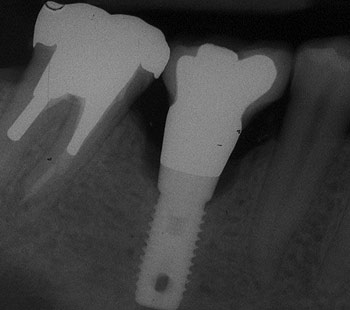

Einzelzahn

Das Implantat übernimmt die Funktion der eigenen Zahnwurzel. Ein ästhetisch ansprechendes Behandlungsergebnis ist hier besonders wichtig. Implantatgetragene, festsitzende Zähne sehen nicht nur aus wie eigene, sondern fühlen sich auch so an.